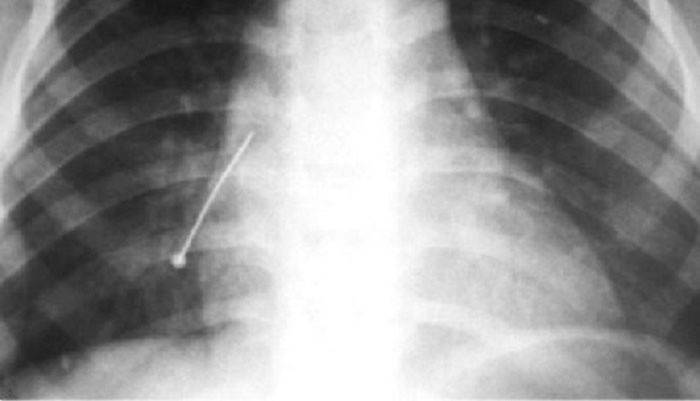

- Em si é considerado um caso terrível e perigoso quando a agulha entra no pulmão ou no coração, fazendo um buraco ali. Se a cirurgia não for feita a tempo, a morte é possível. Nos pulmões (com uma operação atrasada), ocorre inflamação, provocada por uma punção da agulha, que pode levar à perda de parte desse órgão.